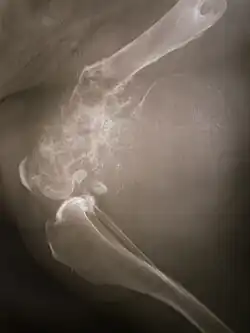

La tumeur est solide, dure, irrégulière, (décrite en « sapin » ou en « rayon de soleil » sur les examens aux rayons X) en raison des spicules tumorales d'os calcifiés rayonnant en angle droit. Ces angles droits forment ce que l'on appelle un triangle de Codman. Les tissus environnants sont infiltrés.

La tumeur peut être localisée à l'extrémité de l'os long. Le plus souvent, elle affecte l'extrémité proximale du tibia ou de l'humérus, ou l'extrémité distale du fémur. L'ostéosarcome tend à affecter les régions autour du genou dans 60 % des cas, dans 15 % des cas c'est autour de la hanche, 10 % à l'épaule et 8 % dans la mâchoire.

Découverte par le chirurgien Alexis Boyer en 1806[5], cette tumeur touche particulièrement les os longs comme le fémur (40 %), le tibia (20 %), le pelvis (10 %), l'humérus (8 %), les os de la face (< 10 %) [6].